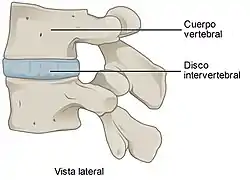

Fisiológicamente, el cuerpo humano tiene diversos tipos de articulaciones, como la sinartrosis (no móvil), anfiartrosis (con movimiento muy limitado -por ejemplo, la columna vertebral-) y diartrosis (mayor amplitud o complejidad de movimiento).

| Anfiartrosis | Escasa movilidad | Cuerpos vertebrales | |

Cartilaginosas

En este tipo de articulación el tejido cartilaginoso sirve de unión entre los extremos óseos, no cuentan con cavidad articular como en las articulaciones sinoviales y el movimiento que pueden permitir es pequeño. Un ejemplo son los discos intervertebrales formados por tejido fibrocartilaginoso que unen entre sí los cuerpos vertebrales de la columna vertebral, la estructura resultante es muy resistente y tiene gran capacidad de absorción de fuerzas, pero no está carente de flexibilidad, por ello la columna vertebral en su conjunto dispone de un grado apreciable de movilidad.[7]

Este tipo de articulaciones se mantienen unidas por un cartílago elástico y presentan muy poca movilidad. Un ejemplo de anfiartrosis son las articulaciones entre los cuerpos vertebrales en la columna vertebral. La sínfisis es un subtipo de articulación cuyas características son intermedias entre las diartrosis y las sinartrosis debido a que pueden presentar una cavidad articular dentro del ligamento interóseo, como la sínfisis del pubis y articulación sacroilíaca.